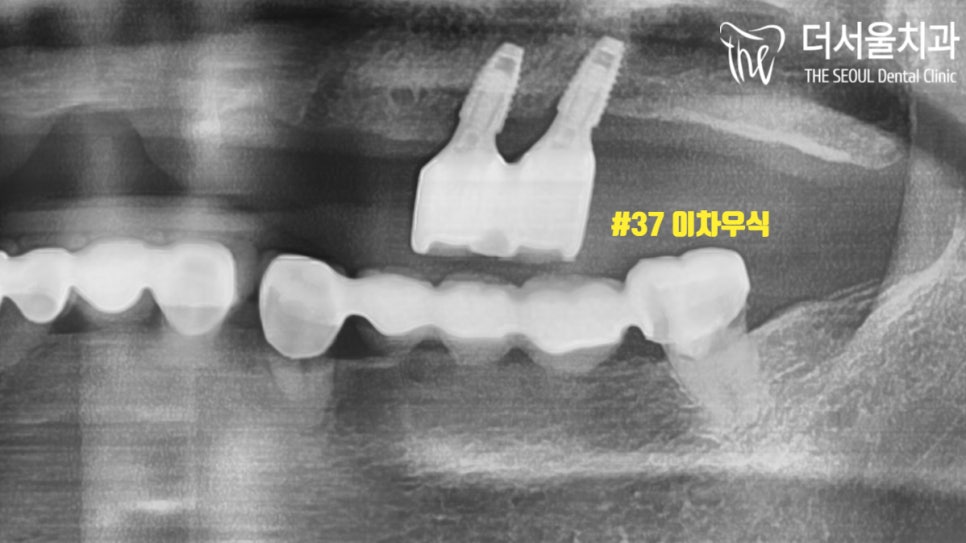

주로 불편함을 느끼고 있었던

왼쪽 아랫니를 확인해 봤습니다.

이런..

단 2개의 치아로

5곳을 연결해놓았네요.

이러니 버틸 수가 없죠.

특히 37번은 많이 썩어있었기 때문에

하루빨리 개선을 해드려야겠다

마음을 먹었습니다.

이와 더불어

오랜 기간 상실된 치아로

꽤 많은 양의 뼈가

소실되어 있었습니다.

검게 바뀌어 있는 모습이

뼈가 없다는 뜻입니다.

원래는 하얗게 차있어야 되죠.